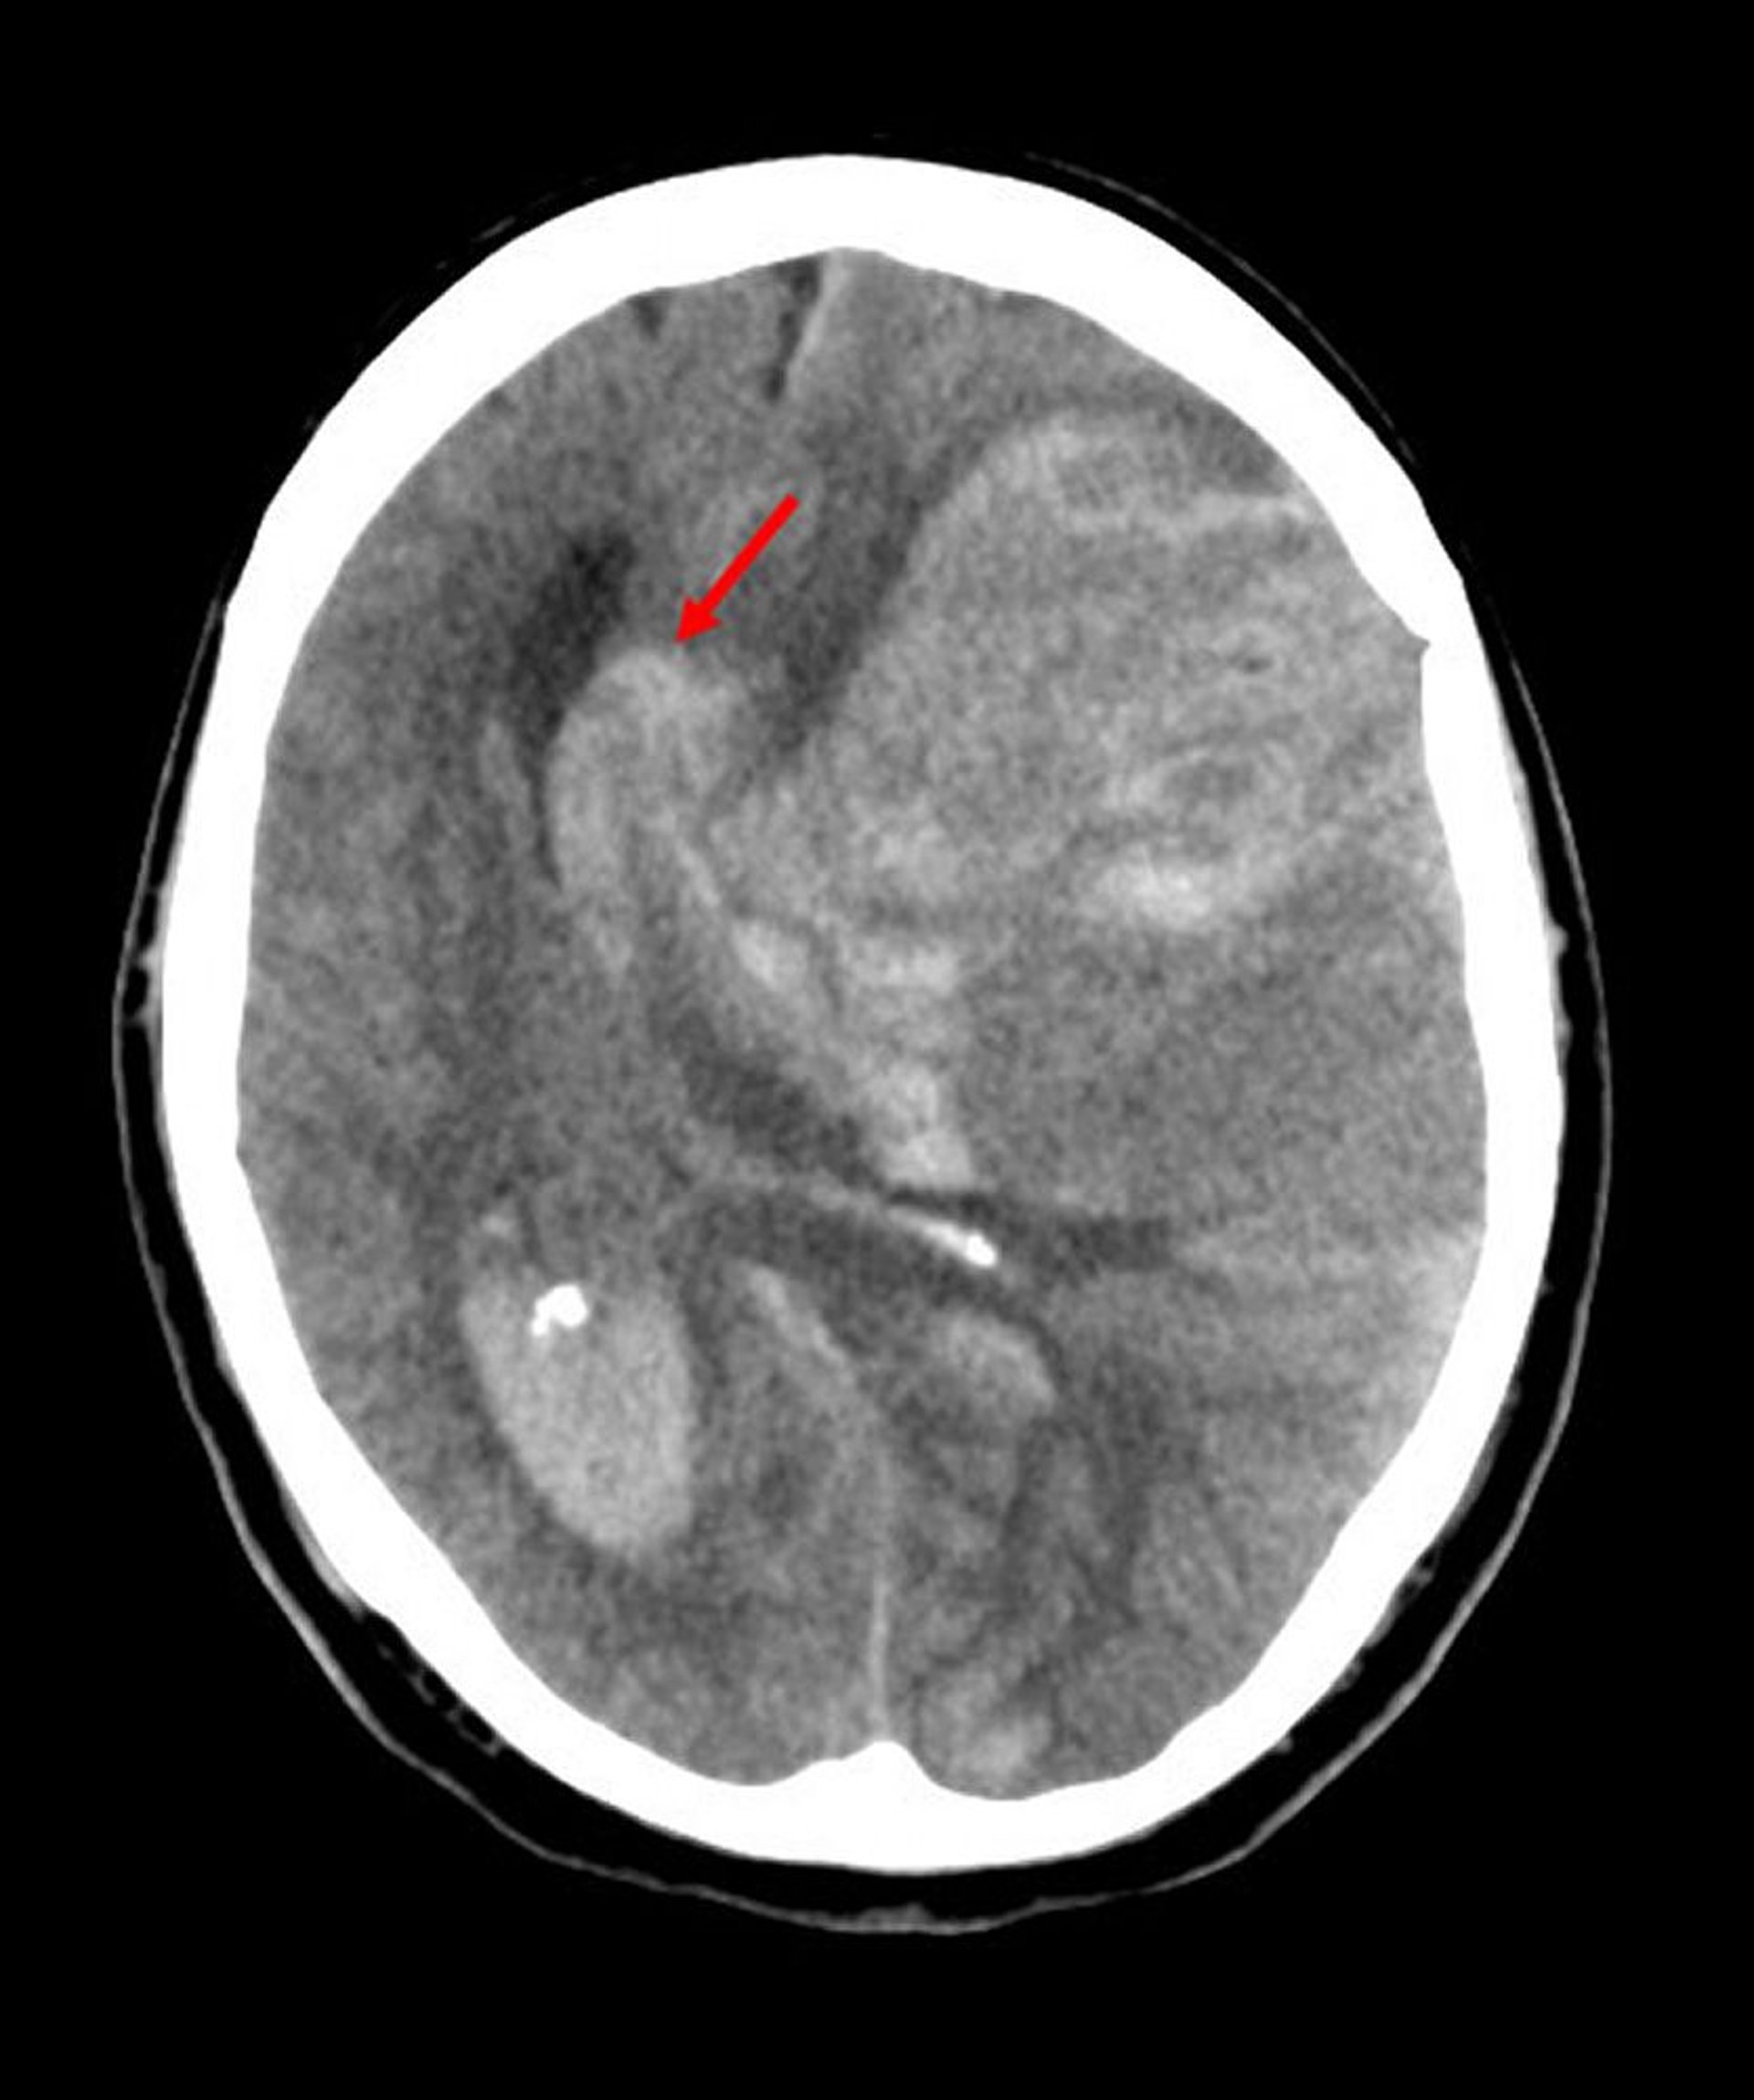

大脳鎌下ヘルニア

大脳鎌下ヘルニアは,最も頻度の高い脳ヘルニアの一種である。この画像では,左脳が大脳鎌の自由縁下に脱出しており(矢印),これは中大脳動脈の梗塞に起因する出血により脳内圧が上昇したことによる。